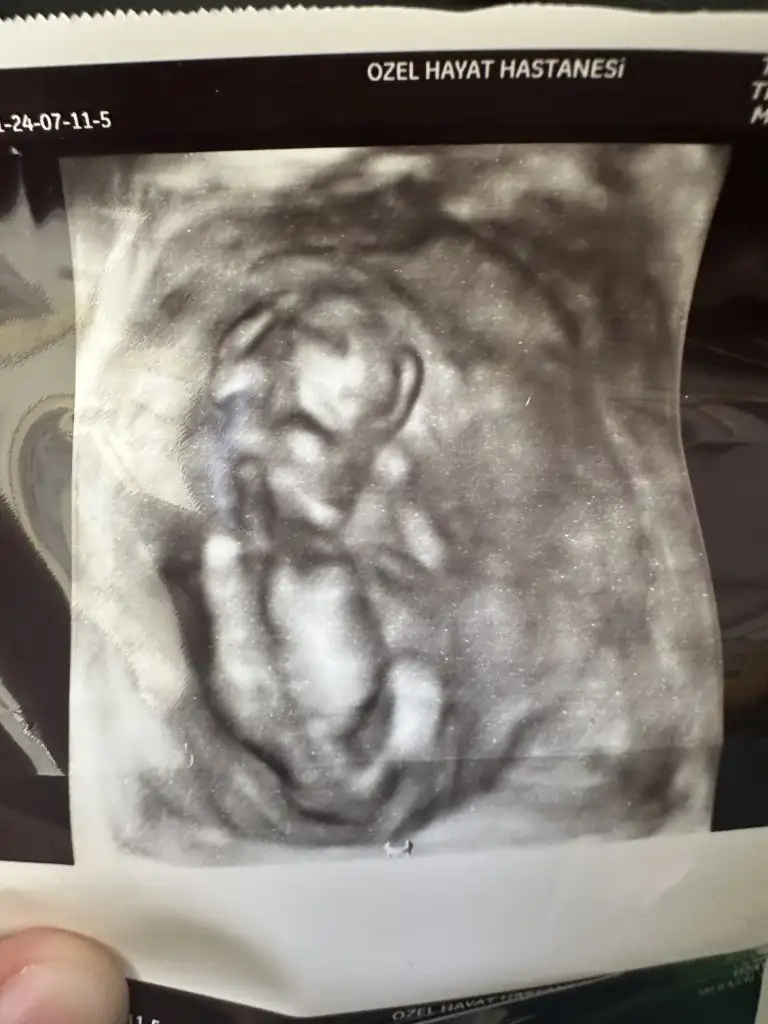

Erkek geldi bana canım sağlıkla büyüsünBana da yorum yaparmısınız güzel hanımlar![]()

Amin canım inşallah kafa yapısından dolayı mı öyle düşündün nub tam belli olmuyor değil mi görüntüdeErkek geldi bana canım sağlıkla büyüsün

Kafa yapısı ve duruş şeklinden canımAmin canım inşallah kafa yapısından dolayı mı öyle düşündün nub tam belli olmuyor değil mi görüntüde

Çok teşekkür ederim canımKafa yapısı ve duruş şeklinden canım

Banada bakabilirmisinizEvet canım hala erkek geliyo bana sırtını dönmüş ama başka var mı düzgün